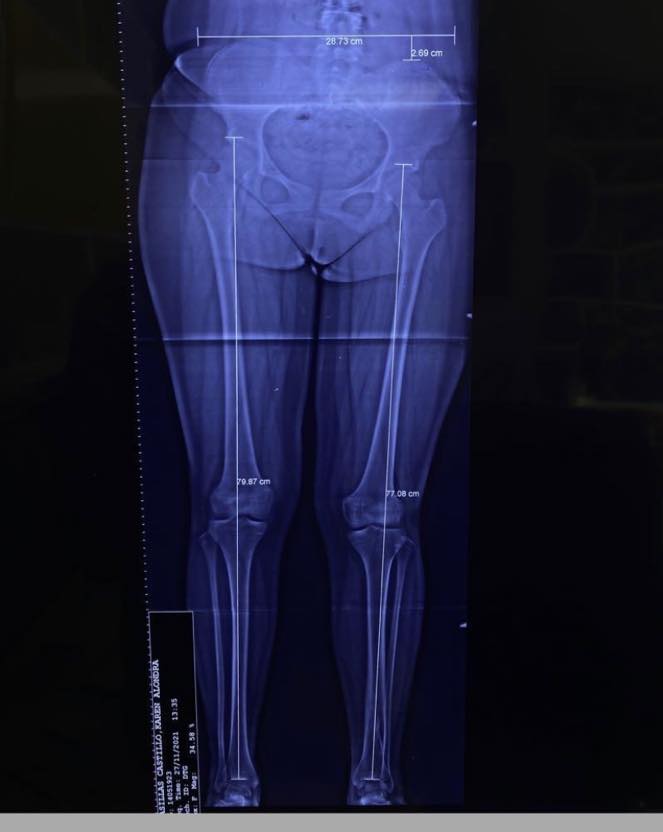

Me complace compartir con ustedes el caso de Karen, una joven de 17 años que acudió a mi consulta por un acortamiento en su extremidad inferior izquierda debido a una fractura de tibia. Después de una evaluación clínica y radiográfica, le realicé una cirugía de alargamiento óseo guiado con clavo centro medular y fijador externo Rekrea. El procedimiento fue un éxito, y Karen recuperó el balance de sus extremidades, eliminando el dolor en su cadera derecha. Ahora, Karen puede realizar todas sus actividades físicas sin problemas y se va feliz y satisfecha. Me siento orgulloso de haber podido ayudarla a recuperar su calidad de vida.